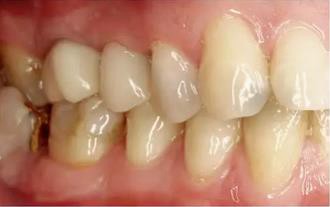

除了純的PMMA基材料(例如:Telio CAD,義獲嘉偉瓦登特,列支敦士登;artBlocTemp,Merz 公司,德國)外(圖1),還出現(xiàn)了各種材料組合。通過使用陶瓷填料,而使材料的性能得到優(yōu)化并適合于長期的臨床使用。為了對不同材料有一個正確的認識,以一個共識會議所提出的內(nèi)容為基礎(chǔ),將在下文對各類材料組合進行探討6。

圖1:單純由PMMA 切削而成的長期臨時修復(fù)體戴入口內(nèi)后的情況。